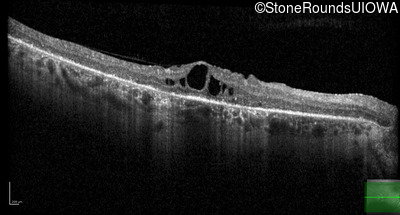

AD Retinitis Pigmentosa (IA1aii)

Age at visit: 60 years

This 60 year old woman first noticed difficulty reading the newspaper about 1 year ago. She also noticed worsening photophobia about that time.

AD Retinitis Pigmentosa PROM1 Arg373Cys CGC>TGC   AD